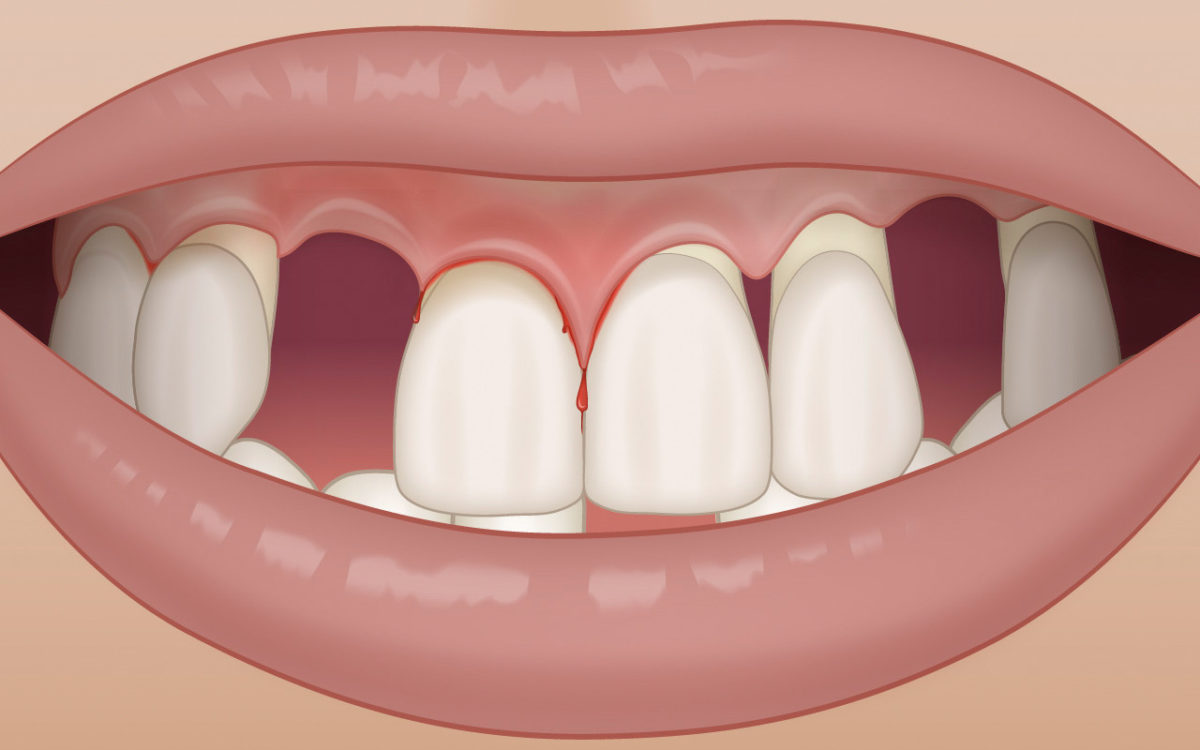

Erste Anzeichen einer Zahnfleischentzündung sind eine Rötung und leichte Schwellung des Zahnfleischrandes sowie ein mögliches Bluten beim Zähneputzen.

Mehr …Zahnfleischbluten

Erste Anzeichen einer Zahnfleischentzündung sind eine Rötung und leichte Schwellung des Zahnfleischrandes sowie ein mögliches Bluten beim Zähneputzen.

Werden die Zähne jedoch bei der häuslichen Mundhygiene wieder regemässig gereinigt, gehen bei einer zuvor vorhandenen Gingivitis diese Zeichen der Entzündung innerhalb von wenigen Tagen wieder zurück.

Sollte das Zahnfleischbluten trotz guter Mundhygiene weiterhin auftreten, sollte das Zahnfleisch zur weiteren Aufklärung in der Zahnarztpraxis untersucht werden.